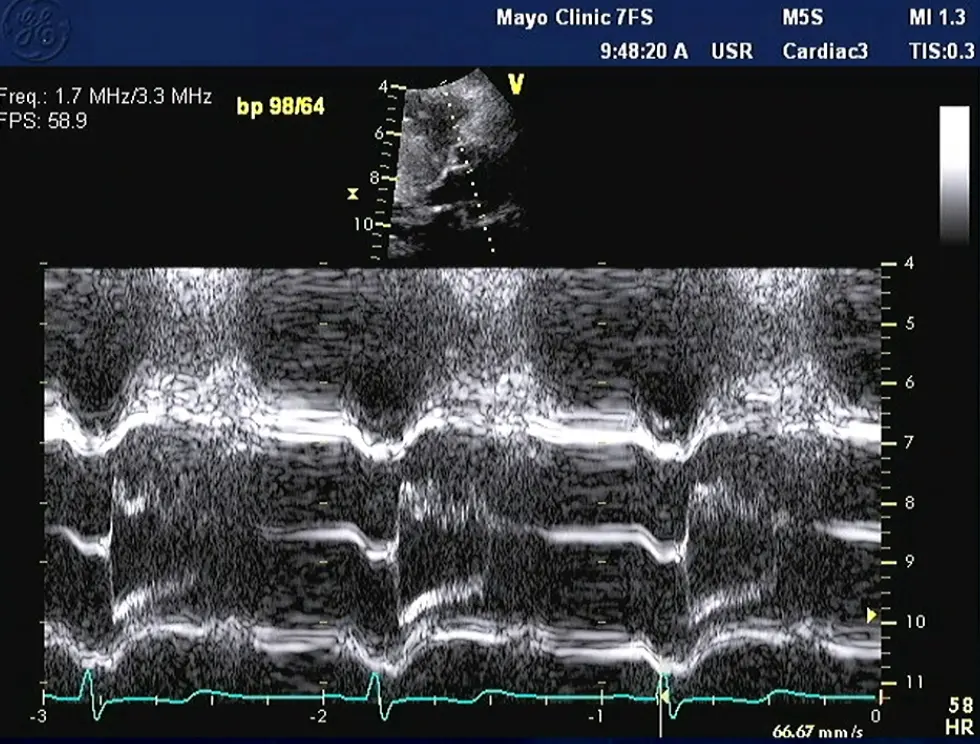

M-mode

- Temporal resolution of M-mode → the duration of SAM where it is in contact with the septum correlates w/ severity of LVOT obstruction

- M-mode in the parasternal long-axis view may assess for midsystolic notching of the aortic valve, reflecting very rapid ejection of LV stroke volume in early systole followed by attenuation of stroke volume in the obstructive phase.